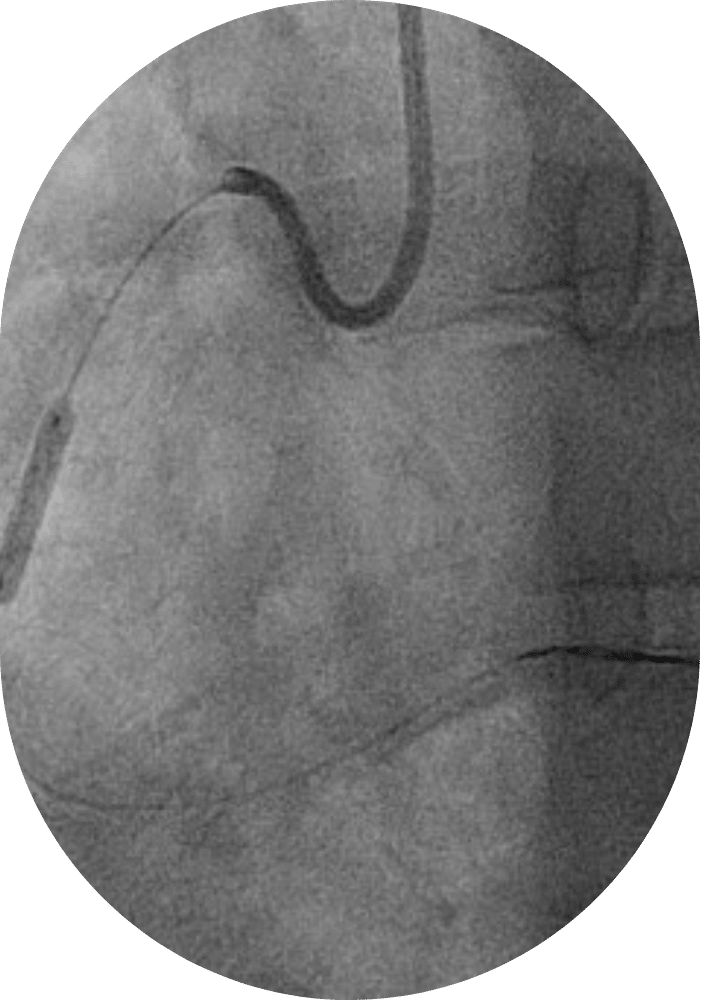

Coronarographie diagnostique

La coronarographie diagnostique est une technique d’imagerie utilisée pour étudier les artères coronaires (vaisseaux sanguins qui entourent le cœur et lui apportent oxygène et nutriments). Elle consiste en l’insertion d’un introducteur de petit calibre sous anesthésie locale au niveau de l’artère radiale (poignet) ou plus rarement au niveau fémoral (aine). Un cathéter (sonde) souple est ensuite avancé jusqu’aux abords du cœur d’où naissent les artères coronaires. Un produit de contraste est injecté pour permettre de visualiser les artères coronaires en utilisant un appareil radiologique. Le cardiologue peut alors évaluer le nombre, la localisation et la gravité des rétrécissements et, le cas échéant, procéder à une angioplastie coronaire ou présenter le patient pour une prise en charge chirurgicale (pontages). Cet examen est réalisé en présence d’un anesthésiste qui réalise une sédation légère pour le confort du patient.